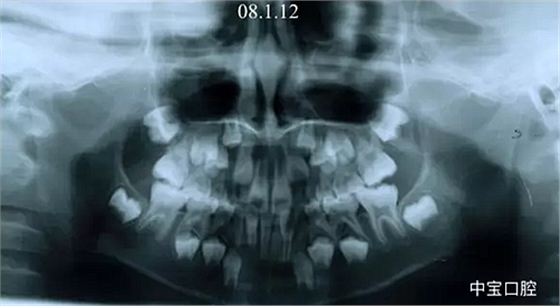

經(jīng)過我臨床檢查和X線的診斷,決定早期干預(yù),每三個月定期復(fù)診檢查一次,并拔掉了幾個乳牙和四個恒牙,正畸專業(yè)叫序列拔牙。